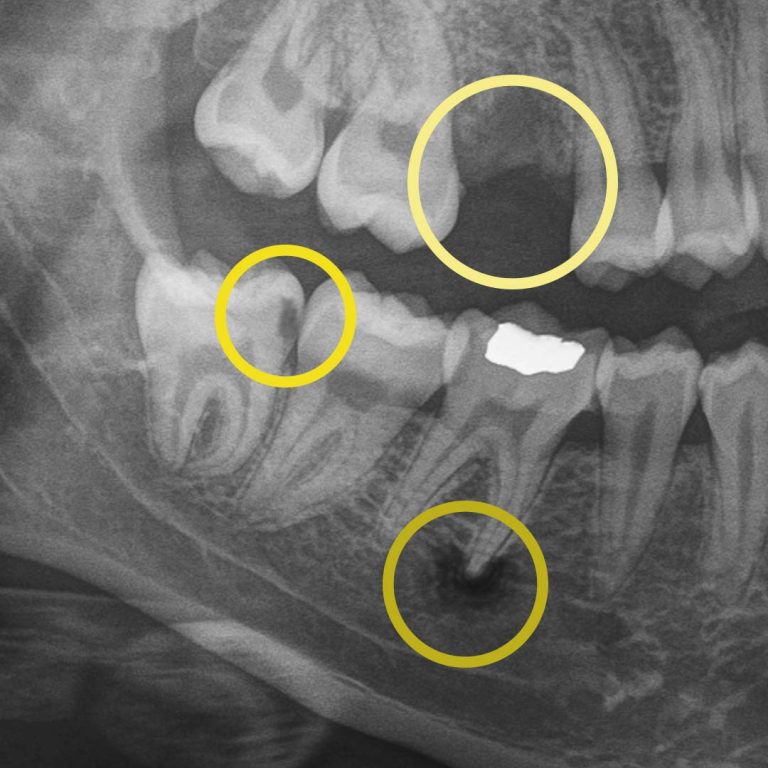

Digital X-rays allow us to look beyond what’s visible. They help us detect:

• cavities between teeth.

• early decay hiding under fillings or crowns.

• bone changes related to gum disease.

• infections at the root of a tooth.

• subtle cracks.

• wear patterns.

• missing primary teeth in children.

For example, during a routine digital X-ray, we may notice a small shadow between two teeth. To the naked eye, everything can look healthy, but that faint shadow often tells us the enamel in that area is starting to weaken. This is considered early-stage tooth decay, sometimes called early “caries.”

At your next X-ray visit, we’ll compare images to see whether that spot has stabilized or improved. If the area worsens and the enamel breaks down further, a small dental filling may be necessary to prevent deeper decay damaging the tooth structure. If the decay continues unchecked and reaches the inner portion of the tooth where the nerve lives, treatment becomes more complex, often requiring root canal therapy, which can be time-consuming, uncomfortable, and costly.